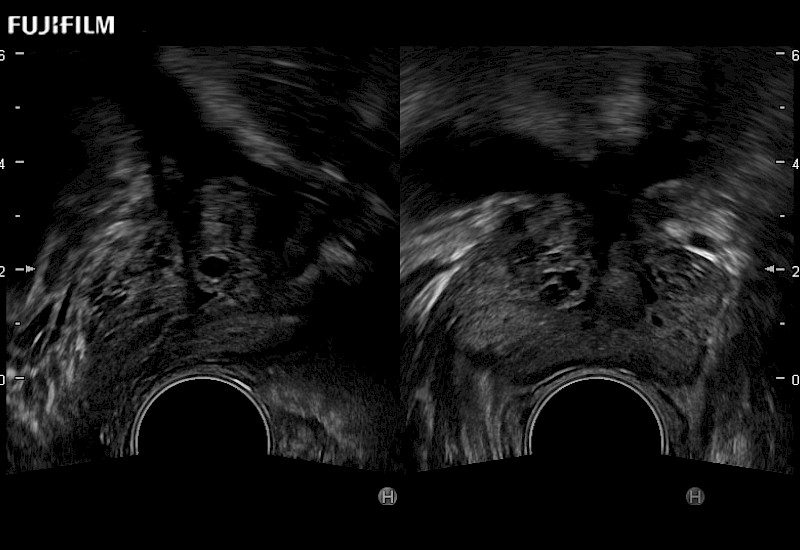

Provides real-time imaging of both the sagittal and transverse planes

Main Specifications: